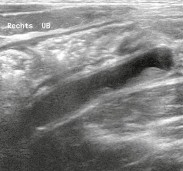

Tiêu chuẩn chẩn đoán của ruột thừa bị viêm là hình ảnh trực tiếp cho thấy sự thay đổi về kích thước của ruột thừa. Dấu hiệu siêu âm có giá trị nhất là thấy đường kính của ruột thừa to hơn bình thường, trên 7mm [35].

Kết quả siêu âm chính xác nhất của viêm ruột thừa cấp tính là đường kính ngoài của ruột thừa >6mm và ấn không xẹp [41]. Ngoài ra còn có một số các đặc điểm hình ảnh khác như: thành dày >3mm, dấu hiệu bia bắn bao gồm các lớp đồng tâm ở mặt cắt ngang và dấu hiệu ngón tay ở mặt cắt dọc [35].

Hình 1.4: Viêm ruột thừa điển hình

Với thành dày và đường kính mặt cắt 9mm [35]